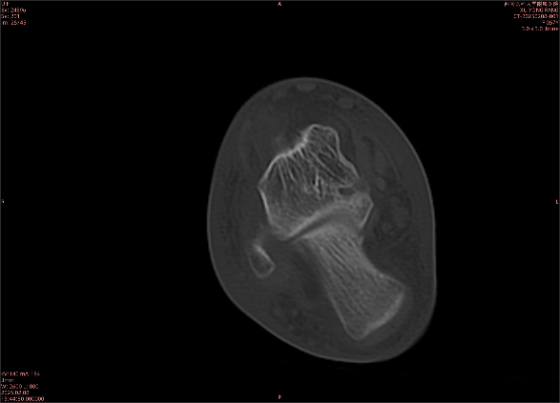

舉例圖像

圖2

專業(yè)解釋看不懂沒關(guān)系,大家看圖1和圖2就可以了,這是同一個(gè)患者跟骨的磁共振和CT圖像,圖1的紅色箭頭指示的黑線就是磁共振圖像顯示的骨折線,一目了然。而對(duì)比圖2的CT圖像上并未顯示異常。